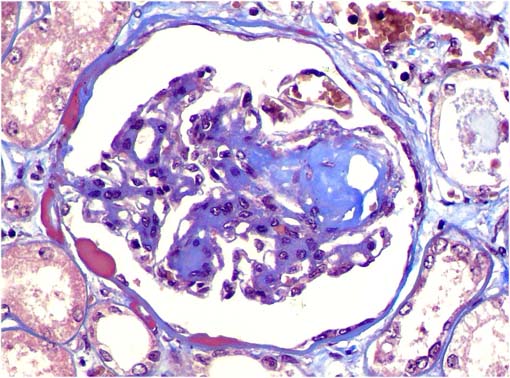

Figura 2.

Tricrómico de Masson, X400.